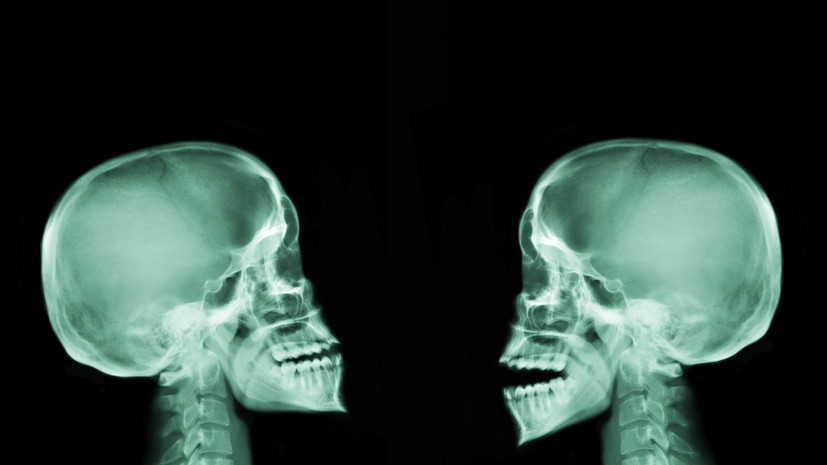

«В результате кости и соединительные ткани, которые должны формироваться у ребёнка, развиваются неправильно. В основном заболевание влияет на кости свода черепа и ключицы», — пояснила Кузнецова.